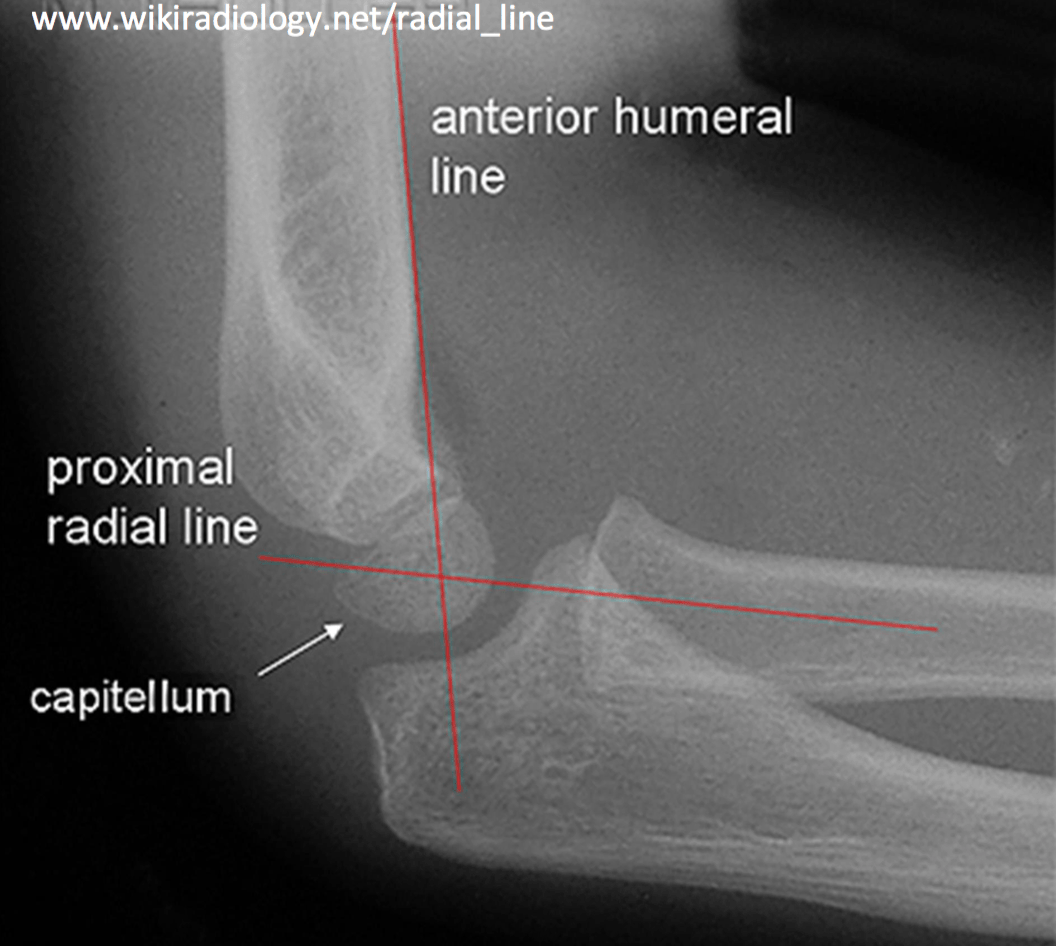

From www.tamingthesru.com

Interpreting Elbow and Forearm Radiographs — Taming the SRU Elbow Joint Out Of Alignment  Elbow instability is a condition in which the elbow joint is loose, causing the joint to slide out of alignment or catch. What is an elbow dislocation? The most common elbow misalignment involves your humeroradial joint. This misalignment occurs from stressful turning motions of the arm like. An elbow dislocation happens when the bones of the forearm (the radius and. Elbow Joint Out Of Alignment.